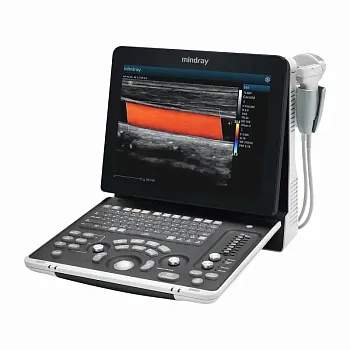

УЗИ аппарат Mindray Z60 портативный

Описание

Аппарат УЗИ Mindray Z60 является новой, переосмысленной версией популярного сканера Mindray DP-50. Аппарат оснащен двумя портами для подключения датчиков и опционально может иметь дополнительный третий порт. Система поддерживает такие продвинутые технологии как компрессионная эластография, а так же 3D/4D исследование и может быть укомплектован более современными датчиками.

Основные преимущества новой системы заключаются в компактном дизайне, возможности регулировки угла наклона монитора до 60 градусов, 15” экран с антибликовым покрытием, жесткий диск 1Т, батарея на 1,5 часа автономной работы, до 3-х встроенных портов для датчиков.